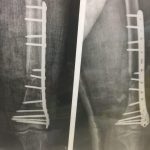

تعویض مفصل زانو و لگن

– شکستگی و در رفتگی